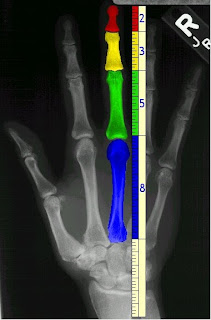

Ο Zeising μέσα από το έργο του καταλήγει στο συμπέρασμα ότι η χρυσή αναλογία είναι καθολική για όλα τα φαινόμενα στη φύση και την τέχνη. Όσο αφορά το ανθρώπινο σώμα ο ομφαλός δεν είναι ο μόνος δείκτης της χρυσής αναλογίας που υπάρχει στην δομή του ανθρώπινου σώματος. Παρόμοιες αναλογίες τηρούνται μεταξύ των άλλων τμημάτων του σώματος όπως το μήκος του ώμου και το αντιβράχιο, το χέρι και τα δάκτυλα, κλπ.